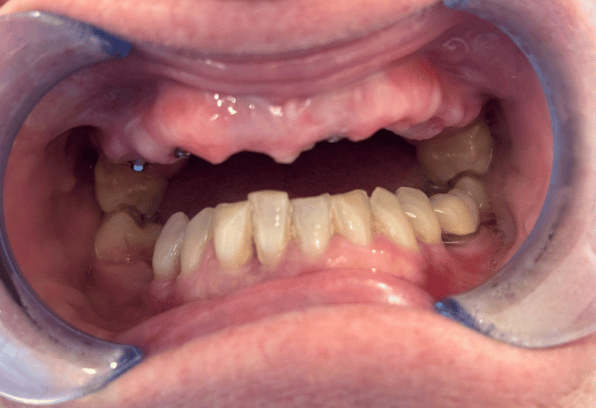

Learn More Before

Before